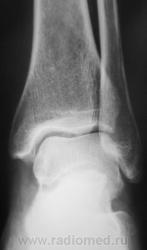

Перелом пяточной кости, перелом н\3 м\б кости, а что это за тень? остеоид-остеома?

Вообще-то в б/берцовой кости стрелка на фоне довольно большого литического очага

На мой взгляд, деструкция есть. Хотя контуры очага довольно четкие, рентгенологический дифференциальный ряд может быть неприлично большим, из серии "и все остальные заболевания костей". Я бы в первую очередь предположила кисту, но м.б. и опухоль. Линейная томография дополнительной информации не даст и их отдифференцировать не позволит: надо узнать что внутри очага - жидкость или ткань. Поэтому лучше всего, до того как поковырять трепаном, сделать МРТ и КТ.

Если серьезно, это вполне может быть и опухоль, например: ГКО, плазмоцитома, хондрома, мтс, даже в начальных проявлениях Юинг или остеосаркома. Диф. ряд конечно поможет сузить клиника. Поэтому пациента стоит "взять на контроль", побеседовать и, когда снимут гипс, без экстрима сделать снимки

Кстати, может быть и остеомиелит. Какая клиника, возраст, были какие-либо симптомы до перелома? Просто, если киста или, к примеру гиперпаратиреоидная остеодистрофия, то можно без трепана обойтись. Хотя трепаном конечно проще...

Вот он, здесь видны четкие контуры очага.